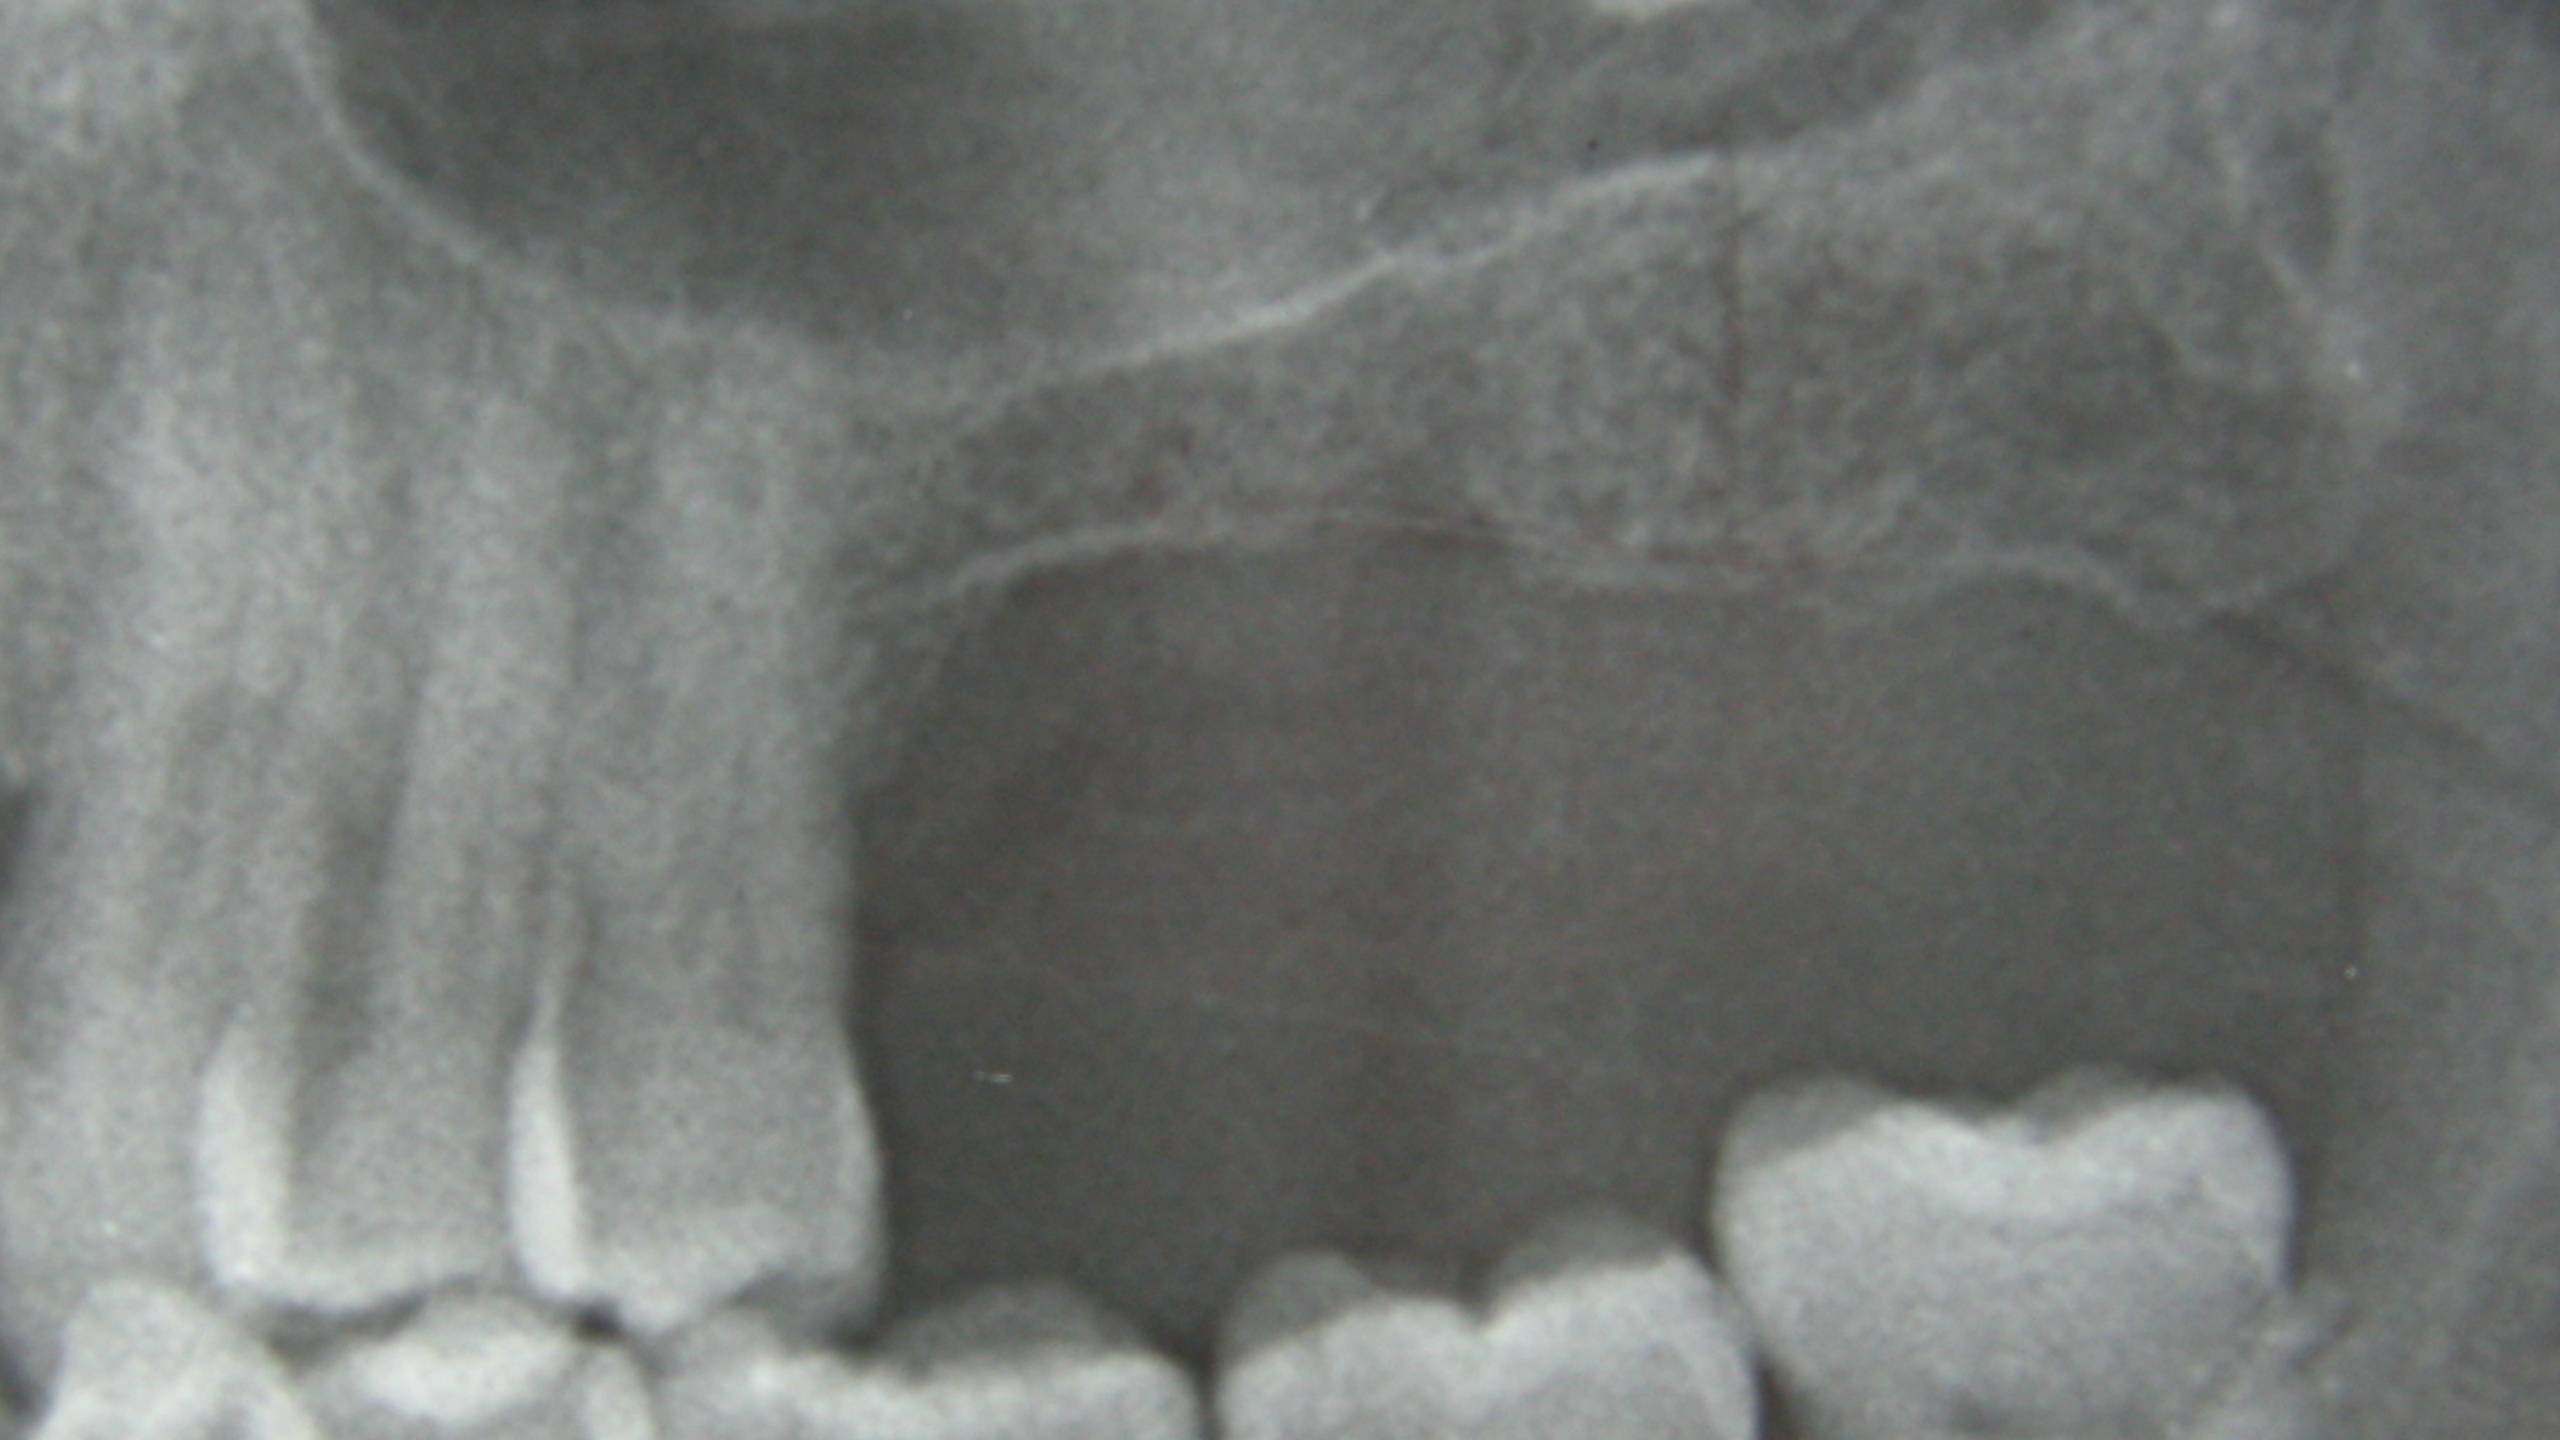

Le sinus radiologique dans tous ses états !

En haut à droite : Sinus sain avec un meat moyen perméable qui permettra le drainage du sinus.

En haut au milieu : Sinus présentant un kyste sous-muqueux.

En haut à gauche : Sinus présentant une Concha bullosa.

En bas à gauche : Sinusite chronique unilatérale.

En bas au milieu : Corps étranger (exemple : pâte endodontique).

En bas à droite : Sinusite par CBS.

Le radio panoramique n’est pas recommandée pour dépister une pathologie du sinus maxillaire, il faut donc s’orienter sur un CBCT et avoir l’ensemble du sinus naso-sinusien.